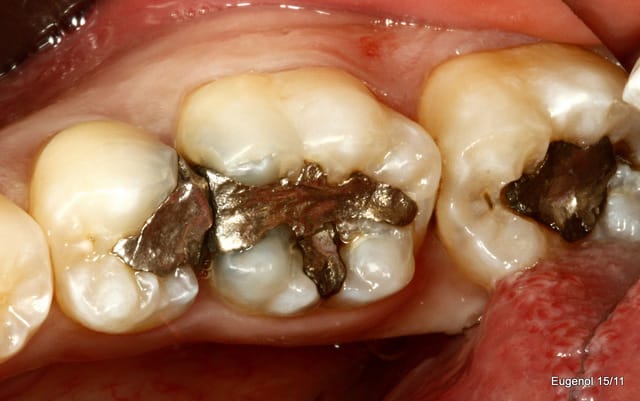

SC12 (35) SC17 (36) sc7 + sc7 (37), 50mn ...

maquillant Enamel HFO